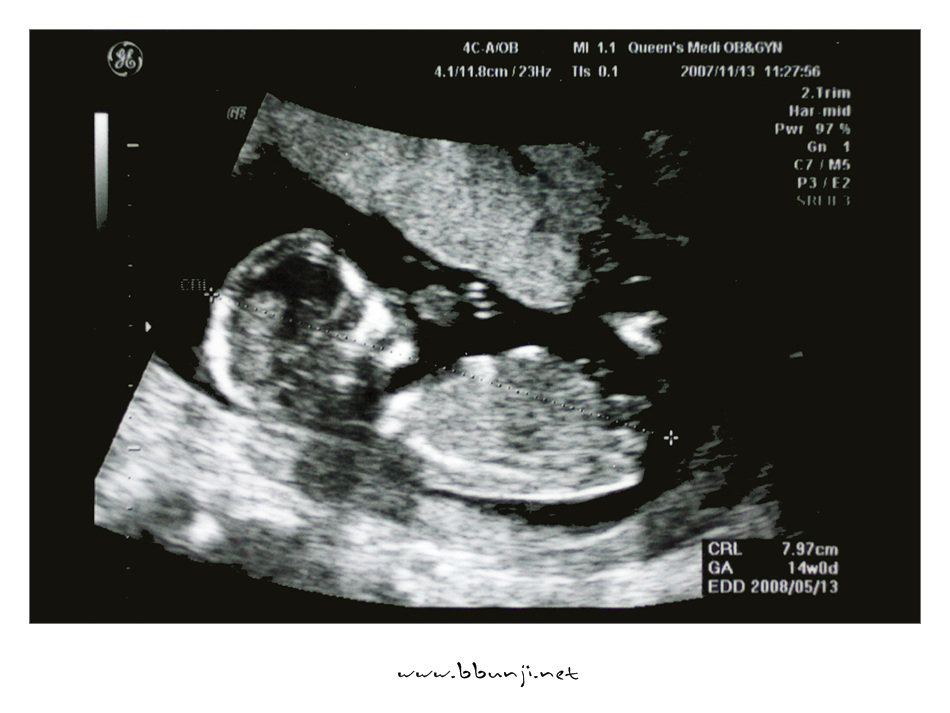

사랑이… 14주 째.. *^^*

2007년 11월 13일

이제 우리 사랑이 제법 키가 커서 8cm가 다 되었습니다.

배초음파를 하는데 첨에는 손깍지 끼고 다리 오므리고 있다가 팔도 움직이고 다리도 움직이더라구요.

이제 척추랑 갈비뼈도 완전히 보이고 손모양도 얼추 제법 모습이 보이네요.

의사 선생님이 코가 오똑하답니다.ㅋㅋㅋ

그 작은 것이 꼬물거리고 심장이 뛰는거 보니 희안하다 못해 신비하기까지 합니다.